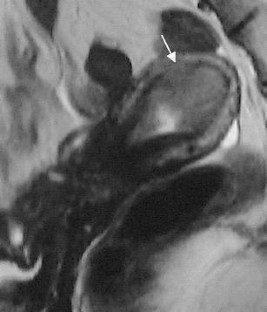

The endometrial cavity may demonstrate various imaging manifestations such as normal, reactive, inflammatory, and benign and malignant neoplasms. We evaluated usual and unusual magnetic resonance imaging (MRI) findings of the uterine endometrial cavity, and described the diagnostic clues to differential diagnoses. Surgically proven pathologies of the uterine endometrial cavity were evaluated retrospectively with pathologic correlation. The pathologies included benign endometrial neoplasms such as endometrial hyperplasia and polyp, malignant endometrial neoplasms such as endometrial carcinoma and carcinosarcoma, endometrial–myometrial neoplasm such as endometrial stromal sarcoma, pregnancy-related lesions in the endometrial cavity such as gestational trophoblastic diseases (hydatidiform mole, invasive mole and choriocarcinoma) and placental polyp, myometrial lesions simulating endometrial lesions such as submucosal leiomyoma and some adenomyosis, endometrial neoplasms simulating myometrial lesions such as adenomyomatous polyp and endometrial lesions arising in the hemicavity of a septate/bicornate uterus, and fluid collections in the uterine cavity (hydro/hemato/pyometra). It is important to recognize various imaging findings in these diseases, in order to make a correct preoperative diagnosis.